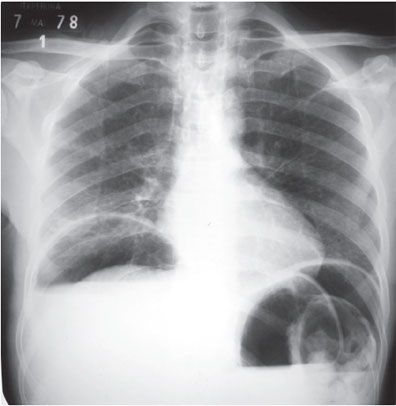

Figura 31.1: Radiografia simples de tórax, em ortostatismo, demonstrando pneumoperitônio bilateral.